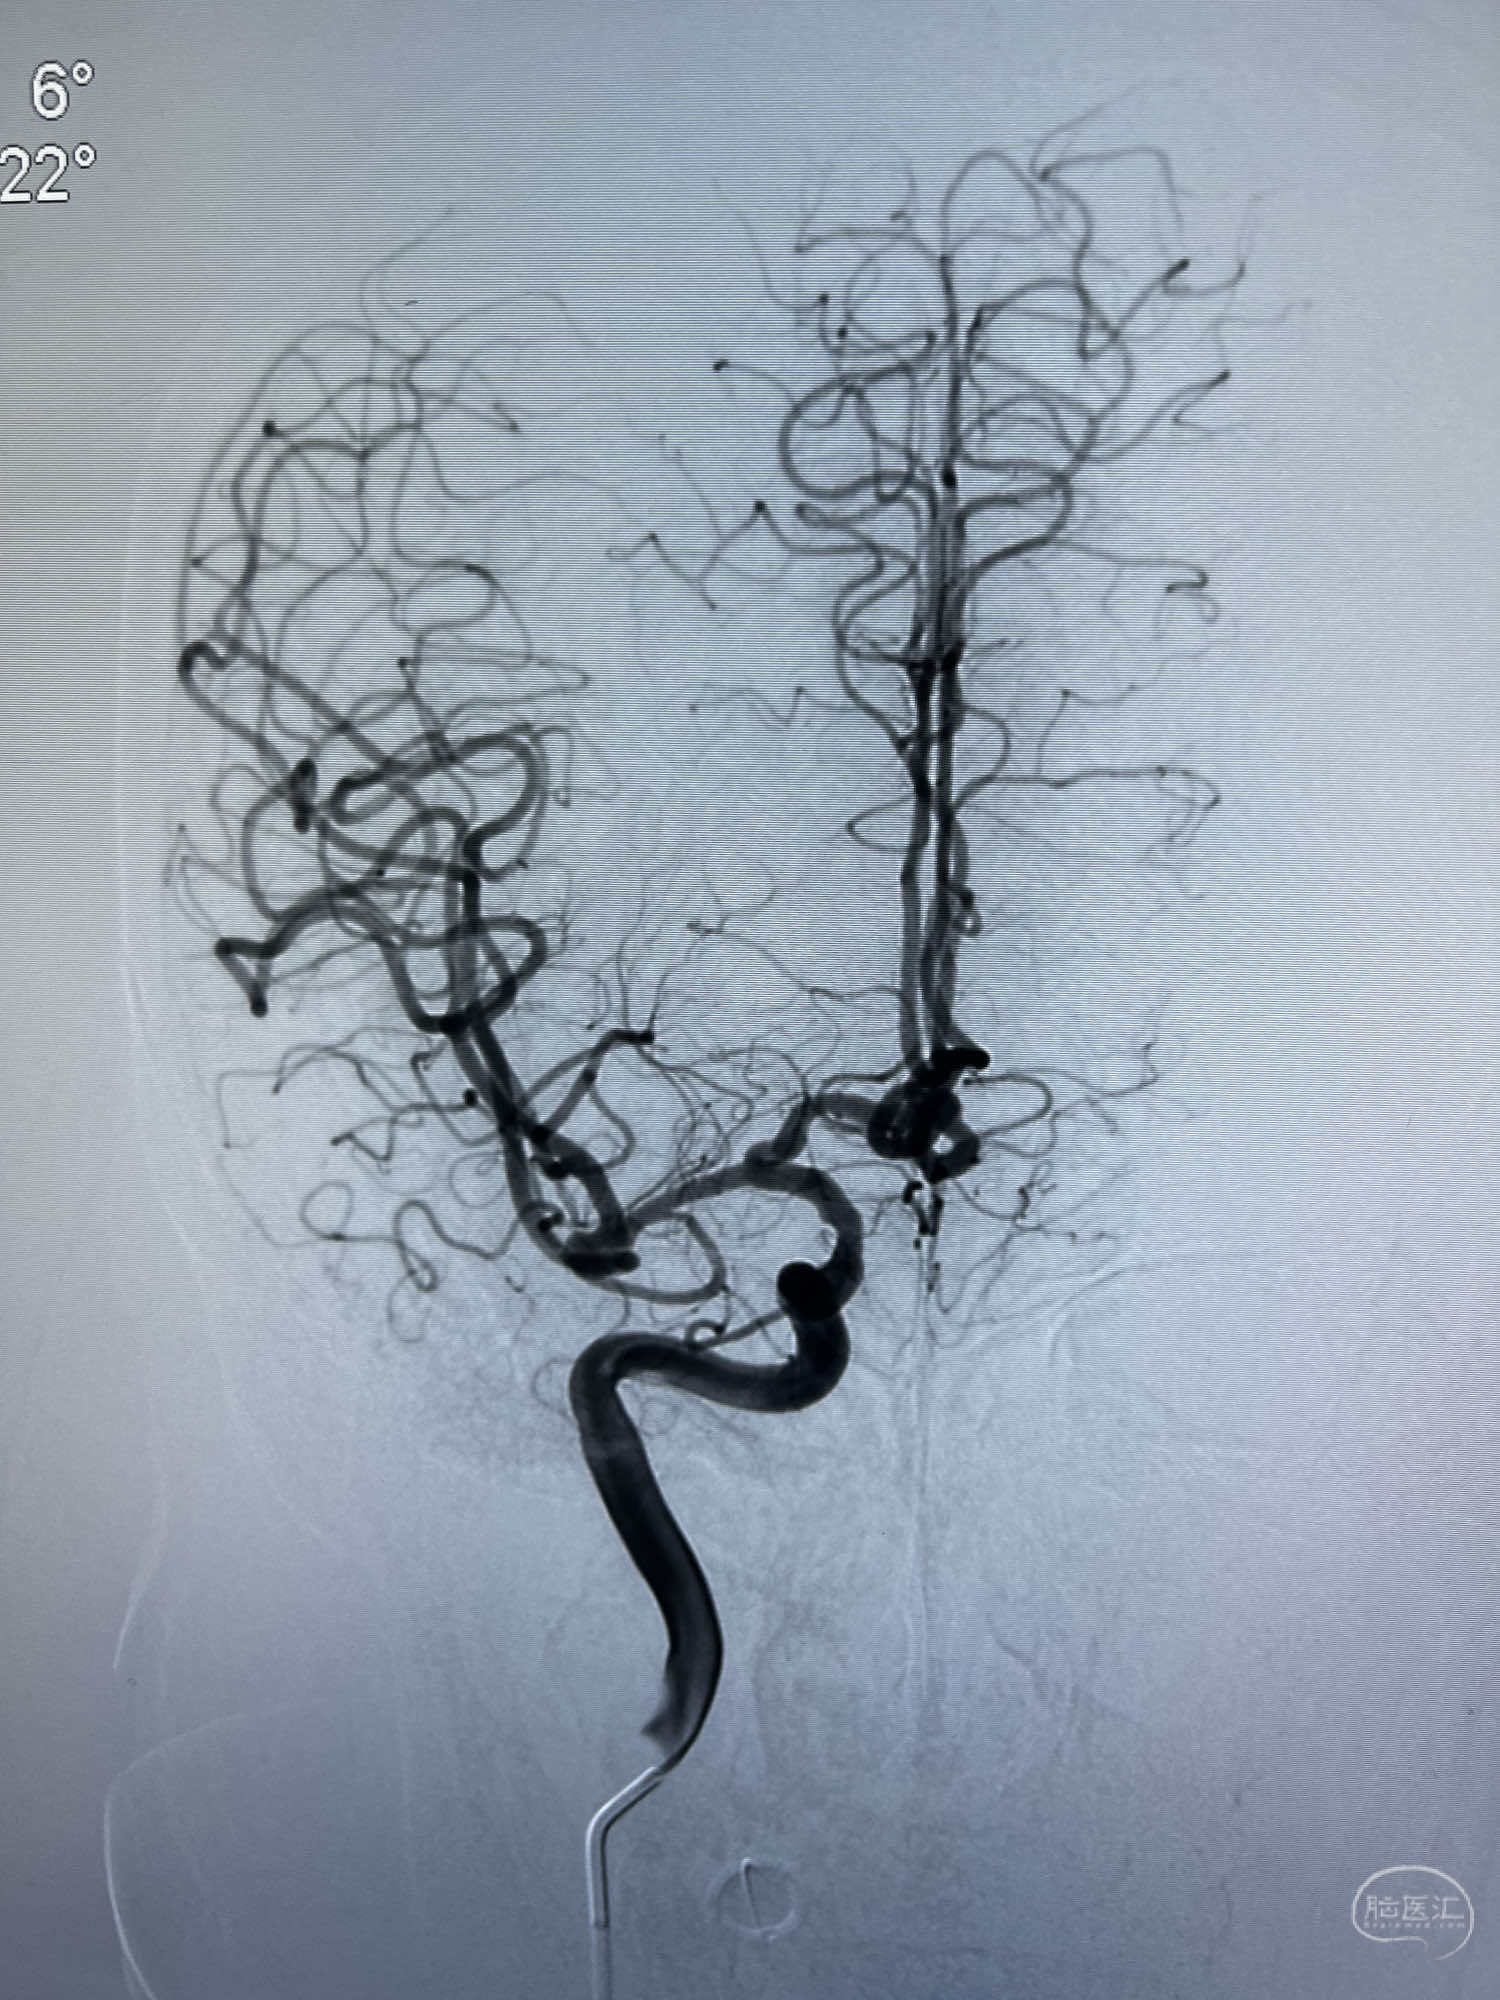

DSA示:左侧颈内动脉眼动脉段以远闭塞,后交通动脉开放,椎基底动脉通过后交通动脉代偿左侧大脑中动脉区域,右侧发出双侧大脑前动脉,右侧大脑中动脉M1末端宽颈动脉瘤,大小约4.3mmx4.6mm。

6F Neuromax➕6F115cm 心玮中间导管建立路径,sychro14微导丝➕VIA21超选至动脉瘤体内近中部,WEB5mmx3mm植入动脉瘤。

WEB瘤内扰流装置5mmx3mm经过“种子、萌芽、开花”三个阶段,打开后良好贴壁,动脉瘤内血液滞留,载瘤动脉通畅。WEB一步到位,通过瘤内扰流的方式起到栓塞动脉瘤的作用,避免了应用支架保护分支血管,简化了操作步骤,降低了术中血栓及出血的风险。